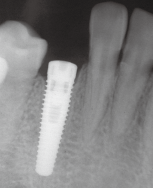

术区常规消毒铺巾,碧蓝麻阻滞加浸润麻醉,牙槽脊顶切开翻瓣,尖钻定位,逐级备洞,植入牙槽窝清创后预备植牙窝,植入种植体(Replace Select®,4.3 mm×13 mm),唇侧缺损处填充自体骨屑。拧上愈合基台,穿龈愈合,严密缝合,常嘱术后4个月后复诊取模,2周后戴牙

拟行即刻种植的病例应符合牙种植术的一般体检要求。适应证包括:①不伴有大量骨丧失的外伤性失牙(本病例);②不能进行牙髓治疗的牙体病 牙;③无法保留的牙周病牙; ④ 根折需拔除的病牙